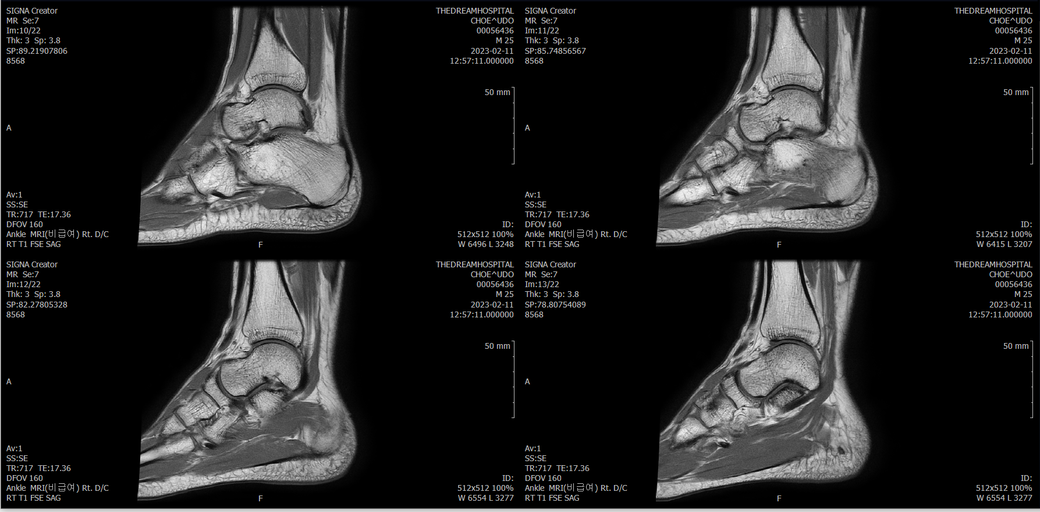

우선 전반적으로 봤을 때 큰 이상은 없어보입니다.

전거비인대 등도 저명한 손상은 없는 것 같아 보이지만, 어느 부분의 통증 등으로 인해 촬영을 하셨는지 말씀을 해주신다면 보다 정확한 병변파악이 가능하겠으며, 병원에서 판독이 완료되신다면 전화 등으로 문의를 해보시는 것이 좋겠습니다.